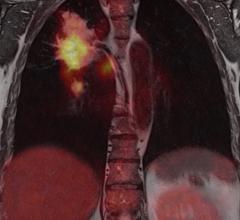

Contributing Editor Greg Freiherr offers an overview of computed tomography (CT) advances at the Radiological Society of North America (RSNA) 2015. The video includes Freiherr during his booth tours with some of the key vendors who were featuring new technology.

Technology Report:

Computed Tomography (CT)